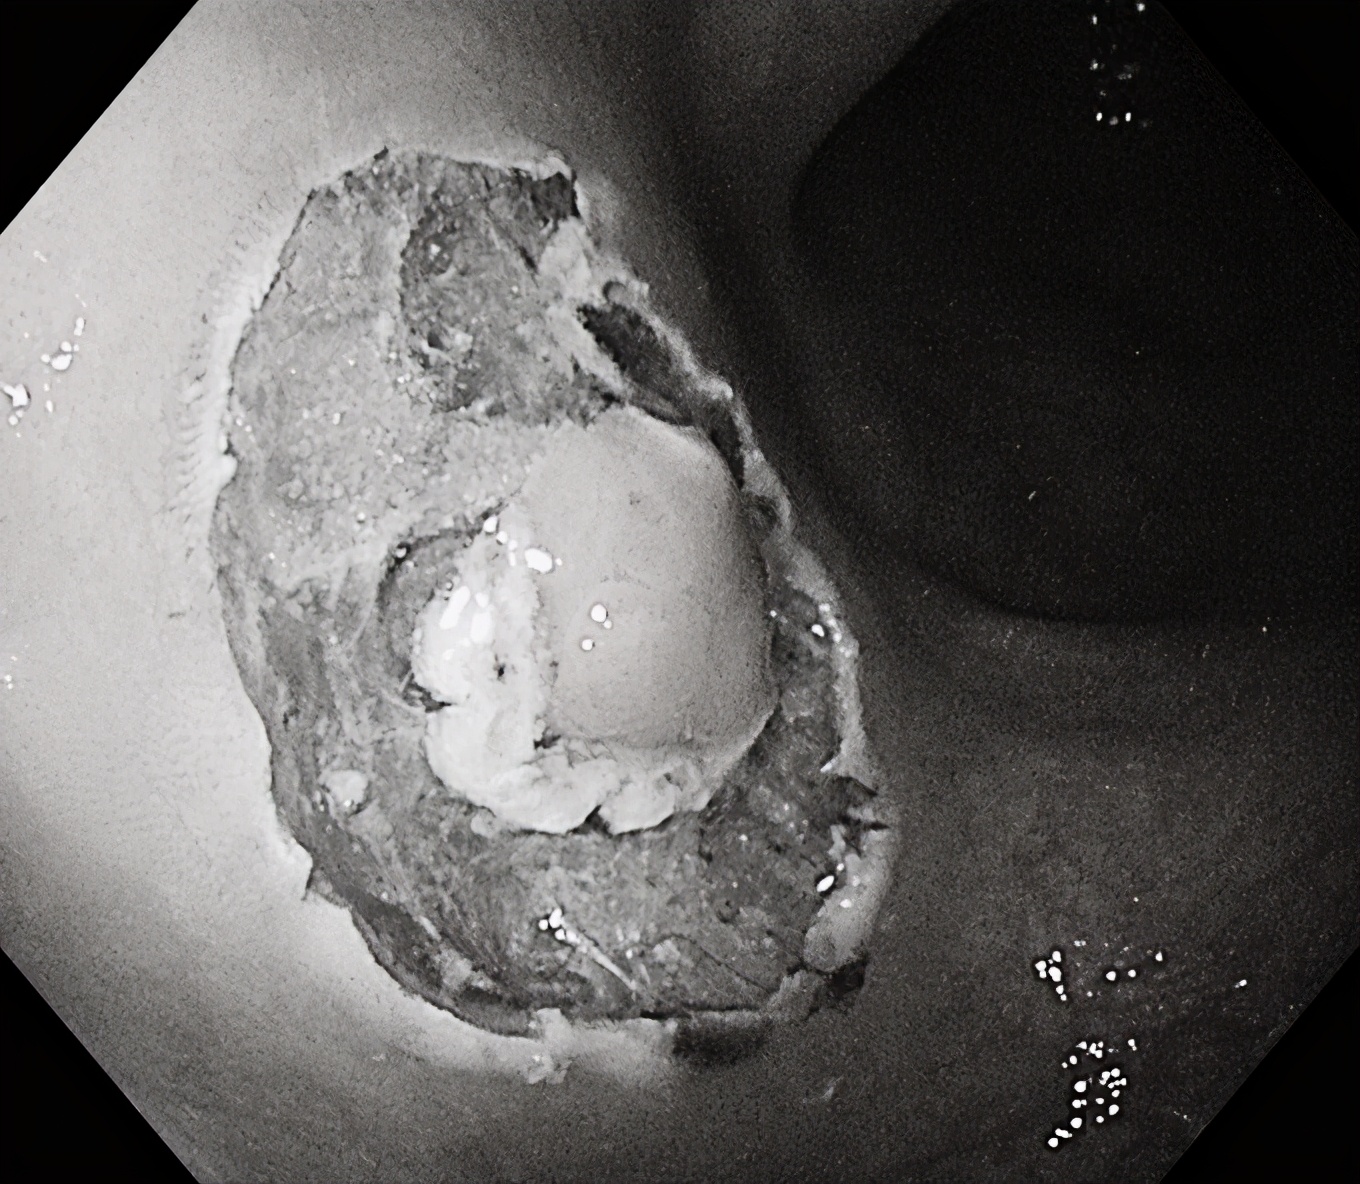

在随后一例肠镜检查中,一名中年女性患者结肠发现3枚无蒂锯齿状病变(SSL),该病变为结肠镜下极易漏诊的结肠癌癌前病变,我们用黄金刀成功施以内镜下黏膜剥离术(ESD)及内镜下黏膜切除术(EMR),完整切除结肠病变,根除了结肠癌的隐患!耗时仅仅10分钟左右,术后无并发症出现,同时送病理检查。

SSL(肠道锯齿状病变),多见于右侧结肠和回盲部,是大肠的癌前病变,癌变率大约10%。

内镜下观察平坦型较多,主要特征:黏液帽(黏液蛋白的缘故)、云雾状外观、扩张的II型腺管(Open II型)、分支扩张、蛇形的血管。当病变出现有蒂或亚蒂、隆起中有隆起、中央明显凹陷、病灶明显发红、合并IIIL、IV、Vi、VN型腺管表现时应想到癌变的可能性。